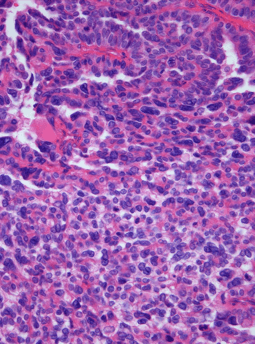

Photomicrograph of hematoxylin-eosin stained section of a choroid plexus carcinoma (grade III WHO) at 400x magnification. | |